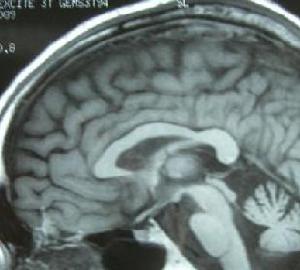

MRI或CT檢查顯示腦幹小腦有不同程度的體積縮小,腦池、腦室有不同程度的擴大及大腦皮質腦溝增寬等也可表現為正常。

夏伊-德雷格綜合症結果: 3例SDS患者均為隱襲性發病,初次就診距發病時間為2~6年,平均4年。3例均有頭暈、尿頻症狀,其中2例有尿瀦留、尿失禁、陽萎和便秘,1例並有暈厥。3例均有直立性低血壓,臥、立位收縮壓下降45~70mmHg(1mmHg=0.133kPa),平均下降58mmHg,舒張壓下降15~25mmHg,平均下降20mmHg。3例均有行走不穩,共濟失調和龍貝格征陽性及下肢單側或雙側巴賓斯基征陽性和查多克征陽性,植物神經檢查,2例患者胸3、4以下皮膚乾燥、無汗,雙下肢皮膚劃痕試驗白色明顯延長,1例患者手足及軀幹皮膚乾燥、皸裂,指甲粗糙。全部行頭顱MRI掃描,2例有腦幹及小腦萎縮,1例行P300檢查潛伏期延長P3b412ms,3例患者行SSR下肢檢查,1例SSR未測出,另2例SSR波幅低限(0.1μV,0.12μV)結果全部異常。